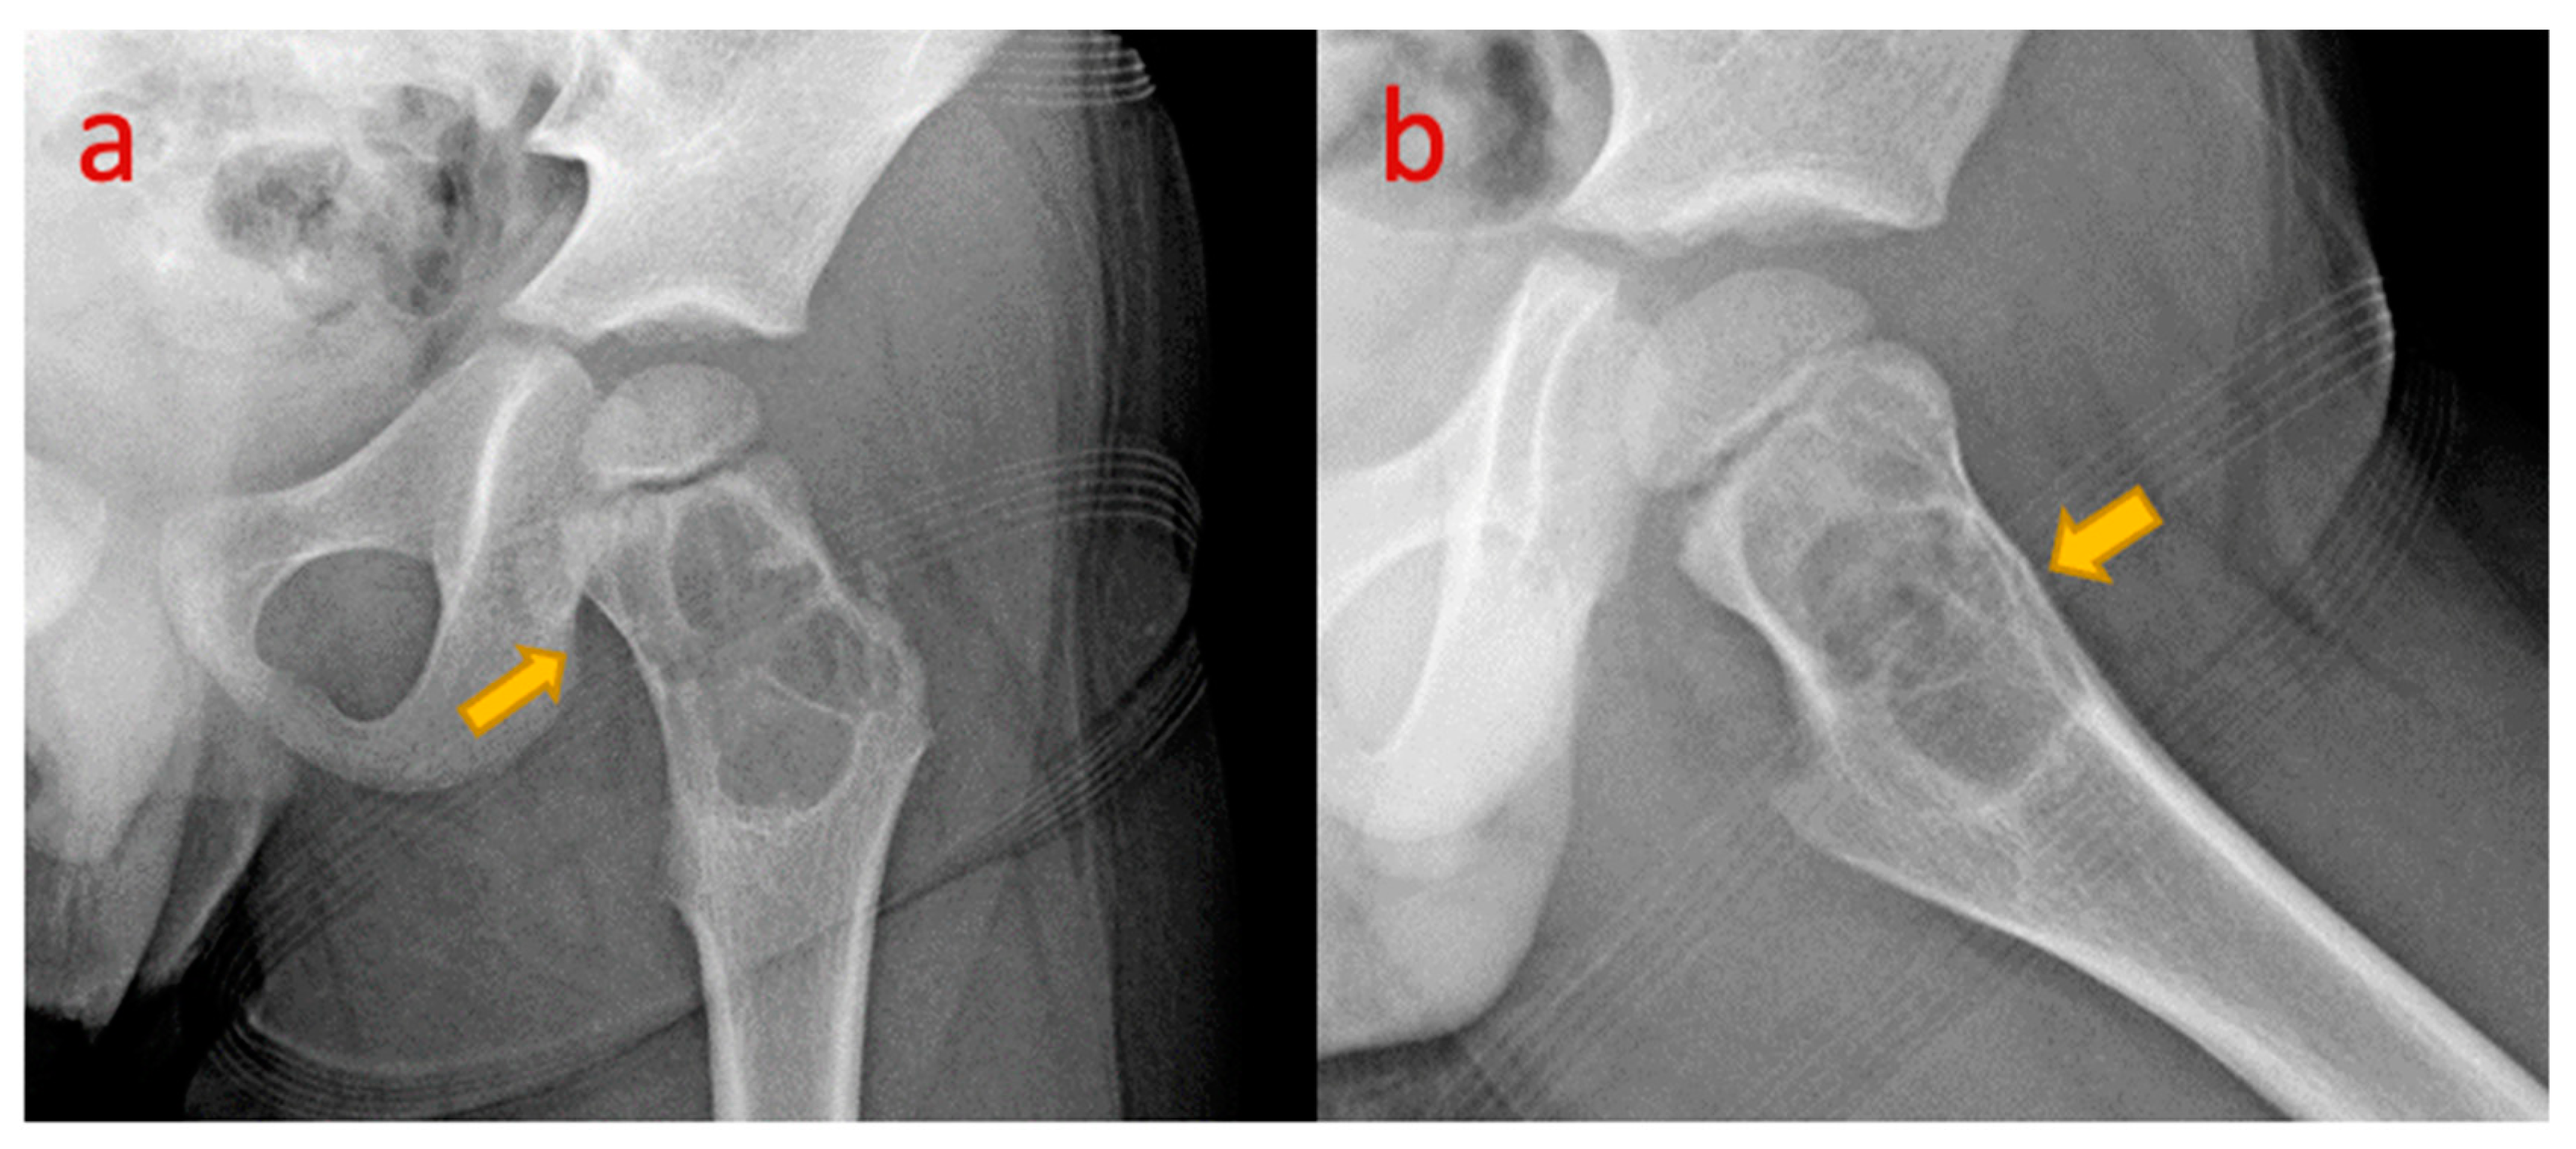

12. Simple Bone Cyst of Neck of Femur